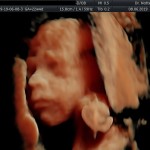

Modalidad de imagen ecográfica que permite evaluar, medir y capturar estructuras fetales superficiales e internas en 3 dimensiones (3D) y también en movimiento y en tiempo real (4D) con programas de realismo aumentado (HD LIVE) e imágenes tomografías fetales (TUI) mejorando significativamente la precisión en las mediciones fetales y la documentaciones de estructuras anatómicas.

Esta tecnología se puede utilizar desde la 6ta a la 40ma semana de embarazo.